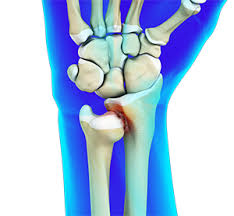

Colles Fracture

Distal radius fracture with fragment displaced posteriorly; often from fall on outstretched hand.